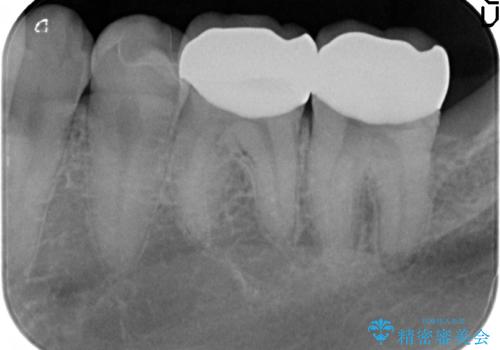

虫歯が大きかったため、被せ物(クラウン)としました。

親知らずを抜いてから治療しています。

- 22万円 (左下67 仮歯1万円x2 ジルコニアクラウン10万円x2)費用は治療当時の料金となります

幸い神経を取らずにすみました。